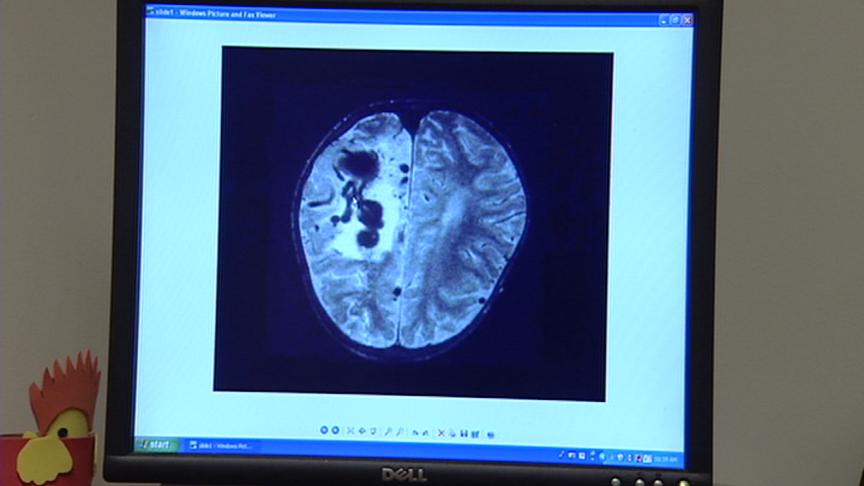

Interventional radiologist Allene Burdett looks at a CT scan of an abnormal tangle of blood vessels in the brain. She sees these in patients all the time because the University of Utah is one of only eight HHT Centers in the country.

HHT is the hereditary syndrome that puts people at high risk for arteriovenous malformations, or AVM's as they're called. Vessels in the brain or lung inflate abnormally like balloons.